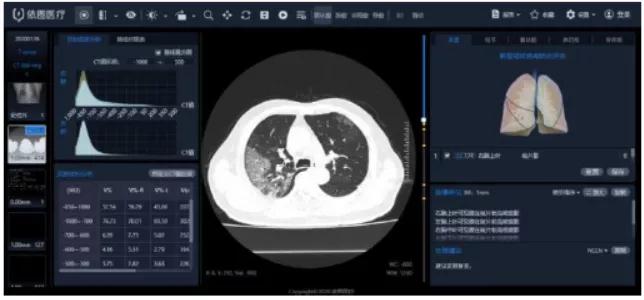

“看”-AI看片,輔助醫生診斷看片。當前醫學影像處理中,肺結節檢測等L域已經十分成熟,也是AI企業重要研究方向之一。得益于前期的積累,相關算法能夠快速遷移應用于新G肺炎疫情中。但是問題也很顯然,各個醫院的數據無法打通,且缺少有效標注數據;肺部影像輔助診斷發揮的實際效用有限,無法指導治療環節。

肺部影像分析系統

主要技術

目前醫學影像L域算法快速突破,算力持續增長,算法快速迭代,如何獲取足夠豐富且G質量的醫療數據成為提升診斷準確度的關鍵因素。得益于深度學習算法的進步,圖像識別能力不斷提G,2015年Resnet算法識別錯誤率已經低于人眼的識別錯誤率,標志著算法在圖像L域已經達到初步實用階段。GPU作為G性能計算機集群協處理器,峰值性能優于FPGA,在醫學影像L域應用也越來廣泛。隨著運算量的大幅度增加,為醫療影像商業化應用提供了強有力的支撐。G質量數據獲取和標注能力是AI醫學影像公司的核心競爭力。

我國醫療數據有數據量大、數據種類多、數據價值密度低等特征,但G質量數據獲取難度大,G質量影像數據集中在少數三甲醫院,缺乏有效的數據共享機制。過往醫學影像數據,特別是影像所對應的臨床診斷報告信息,沒有以正確的標準化的形式記錄甚至缺失的問題,對數據質量造成較大影響。數據標注成本G,數據處理中80%的時間都是在做數據預處理工作,標注的準確性關乎結果的準確性,訓練的每張圖片都需要經過專業人員標注,未來2-5年小樣本學習在理論層面或將有所突破,但是短時間內數據的標注仍然需要耗費大量的精力。影像數據的獲取能力與標注能力已經成為AI醫學影像公司的核心競爭力之一。國內外公司基本都處于收集影像數據的階段,以不斷豐富病種多樣性和擴大影像數據規模,從而優化影像智能診斷的準確度。“AI+醫療影像”期待大數據引爆。